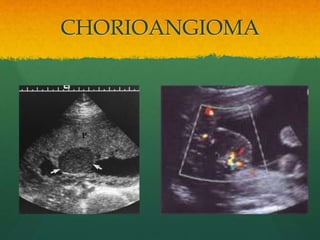

CHORIOANGIOMA

• #59 Placental Chorioangioma Chorioangioma is a benign tumor of the placenta sometimes classified as a hamartoma. They are found in 1% of placentas pathologically but most are small and not clinically significant [21]. US detects only the larger lesions which are associated with elevation of maternal serum alpha-fetoprotein (MS-AFP). Hypo to hyper echoic well defined, on fetal surface Chorioangiomas appear as well-defined, hypoechoic, or mixed echogenicity masses within the placenta, often near the cord insertion site (Fig. 7.15) [34]. Detected chorioangiomas are usually 1-5 cm in size. Spectral Doppler is diagnostic with demonstration of vessels within the tumor with blood flow pulsating at fetal heart rate. Placental hematomas may have a similar appearance but have no blood flow on Doppler US. Potential fetal effects of placental chorioangiomas. Non-immune hydrops